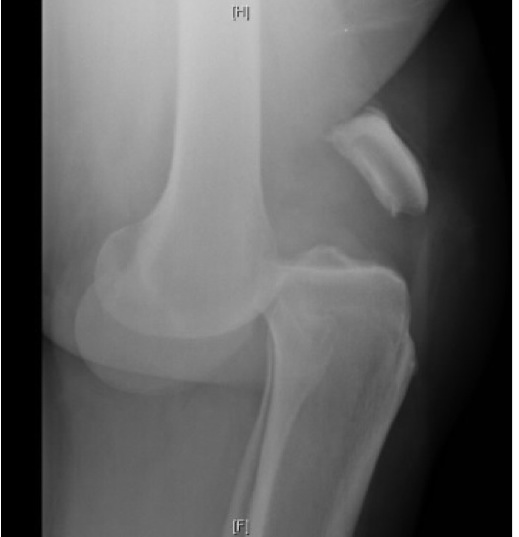

By convention, what direction is the below dislocation?

Anterior dislocation. By convention the distal part of the injury (tibia) is anterior to the proximal part of the injury (femur).